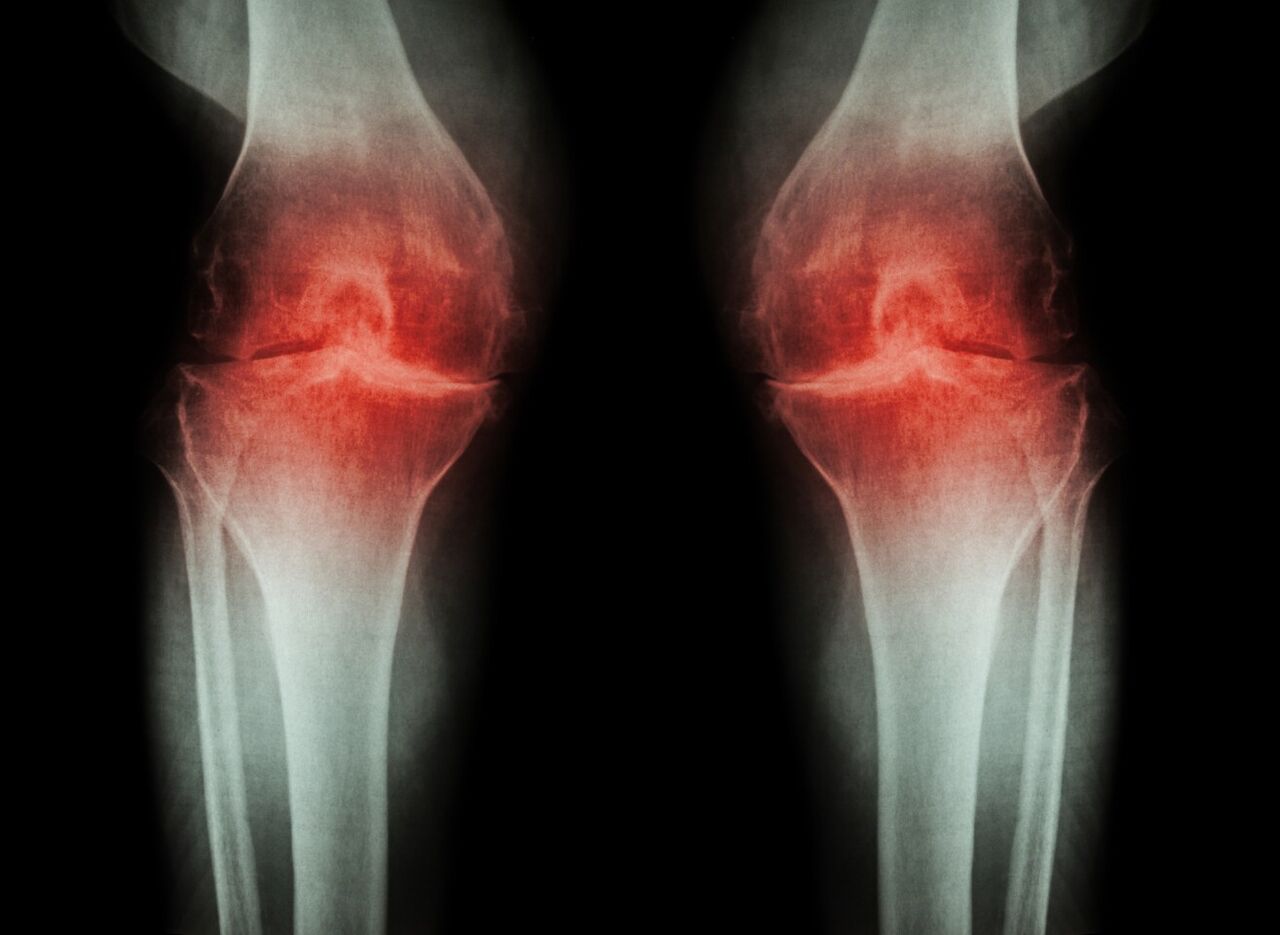

به گزارش روز جمعه گروه علم و آموزش ایرنا از پایگاه خبری ساینس، بین مفاصل به طور طبیعی نوعی روانکننده وجود دارد، زمانی که در بیماری آرتروز میزان تولید این روانکننده کاهش مییابد، مفاصل و غضروفها به هم ساییده میشوند و علاوه بر ایجاد درد، باعث میشود بیمار در انجام فعالیتهای عادی مانند راه رفتن و نشستن با مشکل مواجه شود.

از طرفی بیماری آرتروز عامل از بین رفتن غضروف بین مفاصل است. در این حالت مفاصل و استخوانها هنگام حرکت ساییده میشوند که با علائمی مانند درد، تورم و سفتی همراه هستند.

بر اساس آمار سازمان جهانی بهداشت در سال ۲۰۱۷ میلادی حدود ۲۷۵ میلیون نفر در سراسر جهان به آرتروز زانو مبتلا بودند.